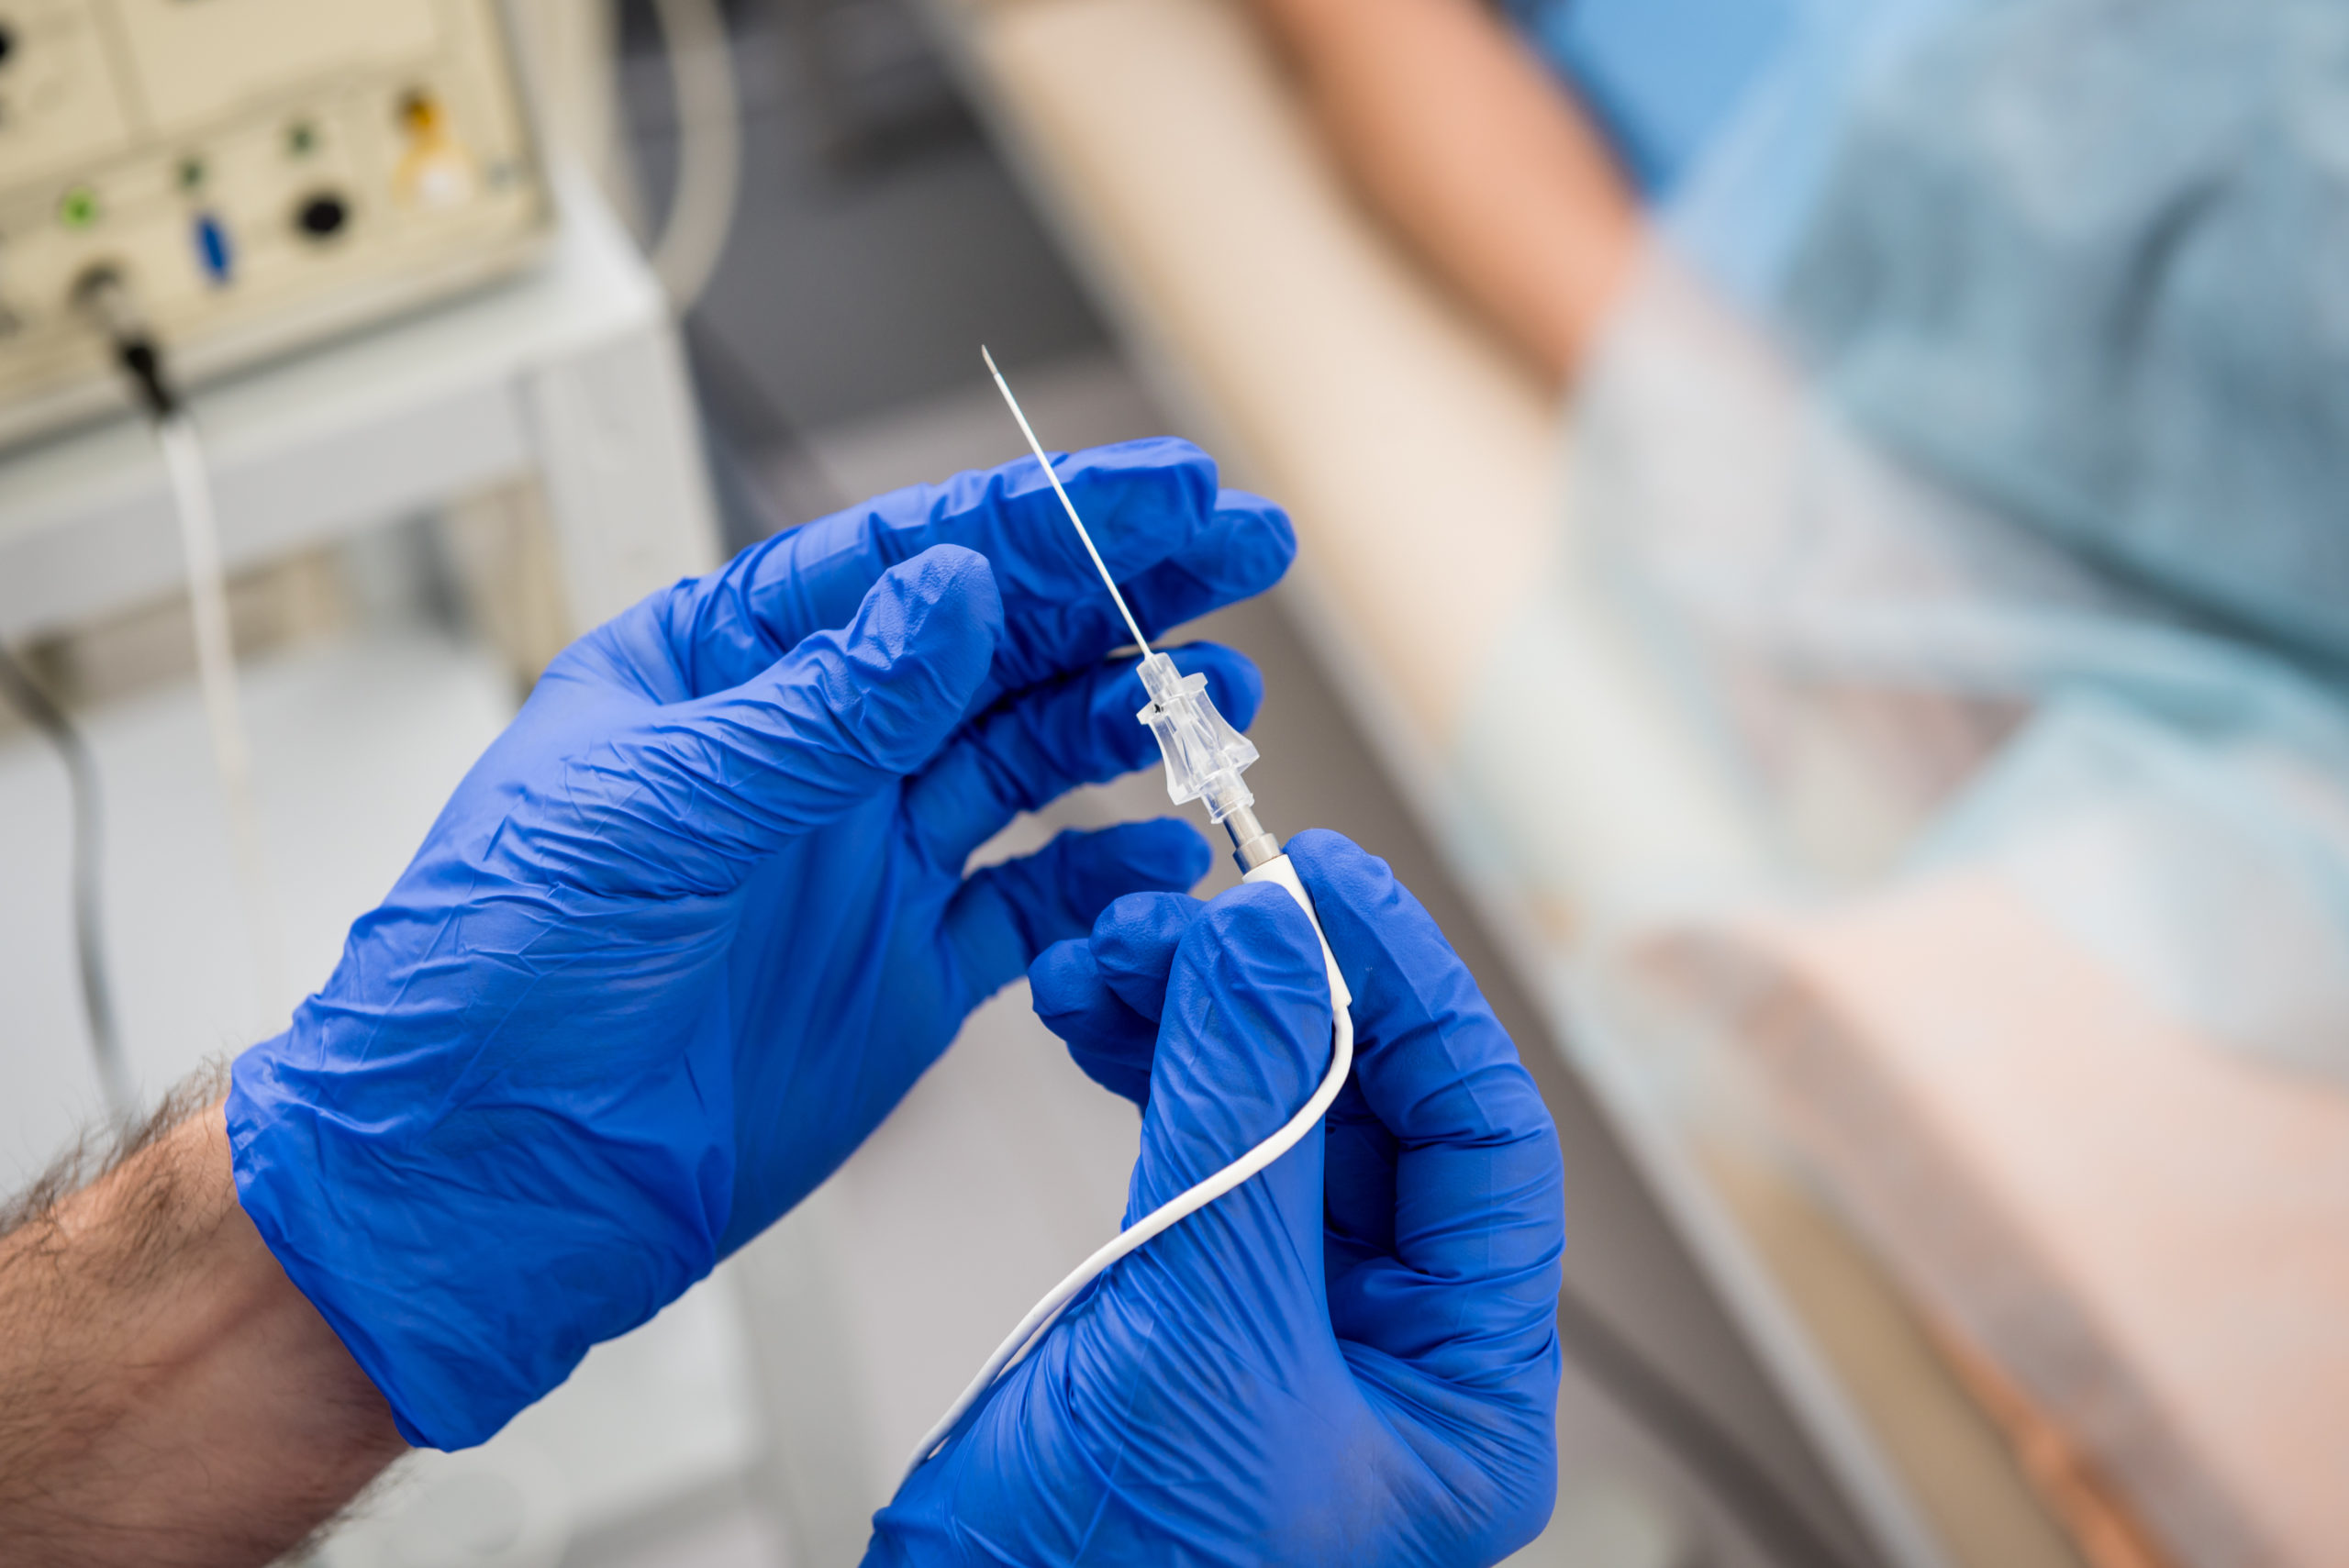

The joint execution of catheter and surgical ablation procedures is a nascent strategy in the treatment of patients with ...

Recently, high-power, short-duration (HPSD) strategies in radiofrequency ablation for atrial fibrillation (AF) have been ...

Pulmonary vein isolation (PVI) via cryoballoon ablation (CBA) or radiofrequency ablation (RFA) is the standard treatment ...

In patients with cardiomyopathy and ventricular tachycardia (VT), early catheter ablation near the time of implantable ...